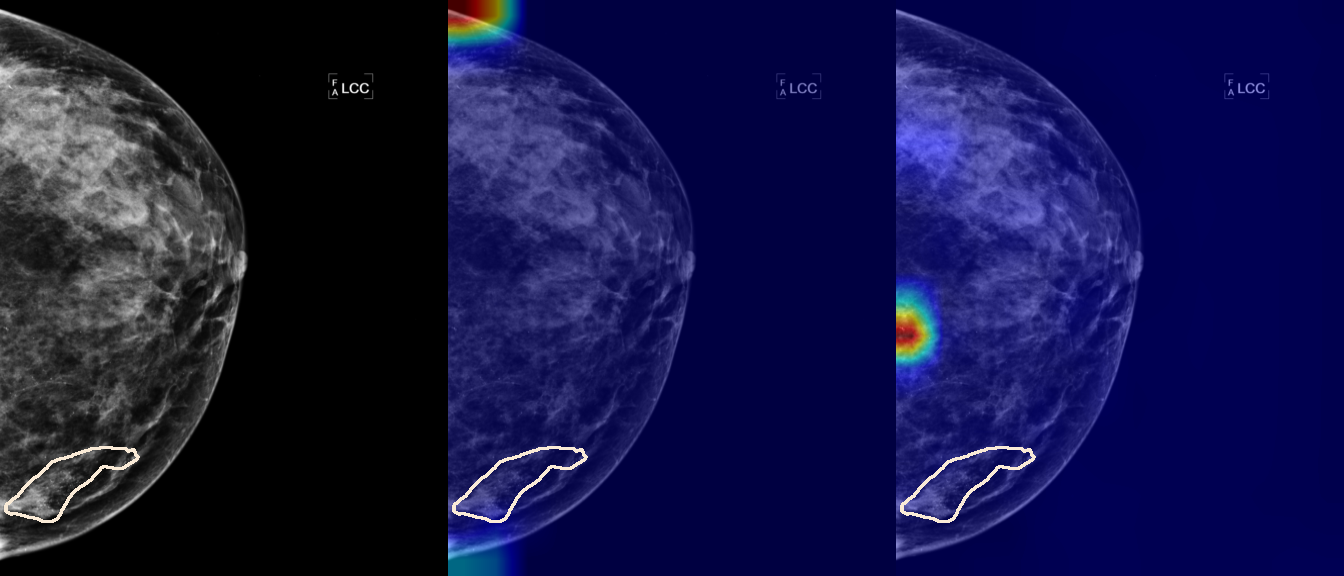

To interpret the decision-making process behind the quantitative results, we visualized Class Activation Maps (CAM) for the top-performing methods, ERM and VREx. Figures 1 through 2 illustrate discriminative regions identified by the models within the full mammograms.

Localization of Clinical Features: A key concern in medical AI is whether high performance stems from genuine pathology detection or spurious background correlations. Our visualizations suggest that Standard ERM achieves its superior quantitative performance by predominantly prioritizing clinical cues. As shown in the top rows of the Figure 1 and Figure 2, the ERM-trained models consistently focus attention on the specific lesion regions within the breast tissue. This demonstrates that despite lacking explicit invariance constraints, ERM is capable of learning robust, medically relevant features when trained on diverse multi-source data.

Attention Drift in Both Methods: While both ERM and VREx generally identify the correct region of interest in successful cases, neither method is immune to attention drift. We observe instances in both training paradigms where the model focuses on irrelevant areas, such as healthy fibroglandular tissue or background artifacts (e.g., rows 5 and 6 in Figure 1). This indicates that while VREx is designed to penalize instability, it does not guarantee perfect anatomical focus compared to the unconstrained ERM baseline.